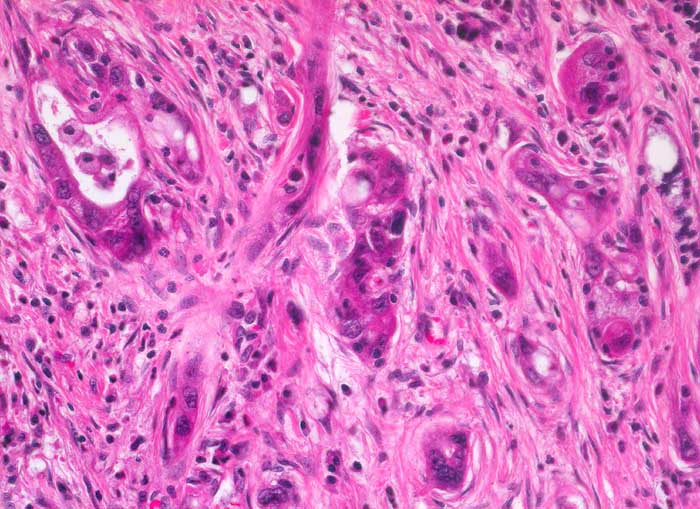

Das Karzinom bildet schlecht geformte oder unvollständige drüsige Strukturen mit ausgeprägten Epithelatypien. Daneben infiltrieren Tumorzellen das Stroma einzeln oder in kleinen Gruppen .

Unregelmässig geformte Drüsen mit unvollständigen Lumina und Einzelzellen oder Gruppen von atypischen Zellen, die das Stroma infiltrieren sind typisch für das Karzinom und sprechen gegen entzündlich bedingte Veränderungen.